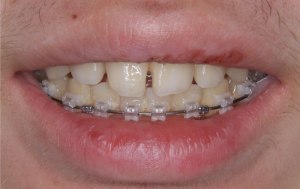

※初診時口腔内写真(全体)

初診時の状態では、上下のいちばん奥の歯がまだ生えそろっていない段階でした。

また、上の前歯が前方に出ている噛み合わせの傾向が見られました。